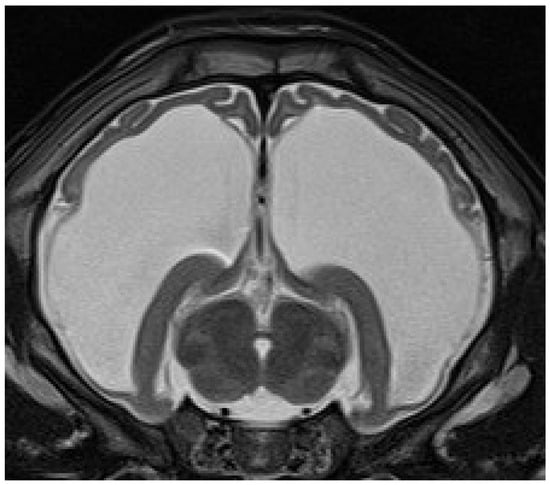

4.6. Imaging

Eleven calves underwent MRI. Imaging identified different stages of cortical parenchymal loss affecting both white and gray matter throughout the hemispheres in all 11 calves (Table 1). The cerebral hemispheres were reduced to a thin rim of tissue in six cases. The remaining cavity was filled with cerebrospinal fluid by a secondary enlargement of the lateral ventricles (Figure 2). These findings are consistent with hydranencephaly. In three cases, there was a severe enlargement of the ventricular dimensions and residual gyrated cerebral tissue was visible, consistent with severe internal hydrocephalus (Figure 3). Two calves showed no or only mild ventricular enlargement with normal gyration of the cerebral tissue. In these two cases, a reduced contrast between white and gray matter was noticeable and focal hyperintense areas in the white matter were visible. Impaired cerebral myelination or focal leukomalacia were suspected.

Figure 3. Transverse T2-weighted MRI of a brain at the level of the thalamus and hippocampus of a 28-day-old male calf with obtundation, absent menace response, proprioceptive ataxia, and proprioceptive deficits. The cerebral hemispheres are severely reduced and residual gyrated cerebral tissue is present. The remaining ventricular cavity is markedly enlarged and filled with cerebrospinal fluid. These findings are suggestive of severe internal hydrocephalus.